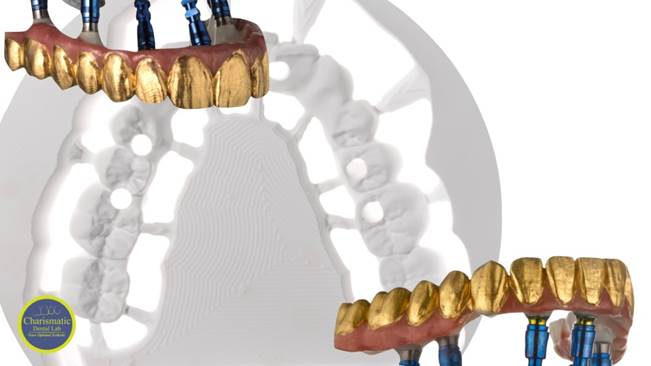

“AnyRidge shows excellent esthetic results

with Zirconia prosthesis in full-mouth rehabilitation case . ”

Clinical case: A Full transition from natural teeth to all-on-6 bridges

with AnyRidge implants

- Courtesy of Dr. Rabih Abi Nader, UAE -